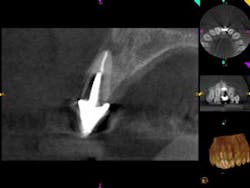

A 60-year-old male patient presented with a buccal swelling in the maxillary left anterior. Clinically the patient had a three-unit bridge connecting Nos. 7–9 (figure 1). The patient was happy with the esthetics and wanted to save his natural dentition. The recommendation was made to take a narrow-field CBCT scan to evaluate No. 7 in three dimensions. The CBCT scan showed that the apical disease had led to root resorption at the apical third of tooth No. 7 on the distal root surface (figure 2). This was invaluable information that allowed me to make the best approach to the root surface while keeping the osteotomy as small as possible. It also allowed me to have a three-dimensional view of No. 7 before even beginning the surgery, which helped to aid in proper root resection to conserve as much sound tooth structure as possible.

After root resection, root end prep and the placement of biologically compatible root end filling, the osteotomy was grafted (figure 3). Because of the size of the apical disease, along with the large cast post and the resorption, traditional nonsurgical retreatment was not a viable option for long-term success. With the aid of the CBCT imaging, it was already noted where the root end filling needed to be placed not only to seal the distal defect but to seal the true apical terminus.